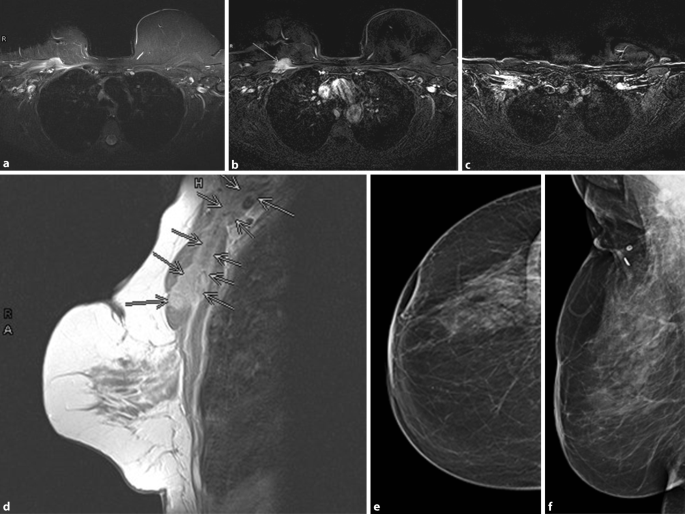

Senologische Diagnostik In Einem Zertifizierten Brustzentrum Springerlink